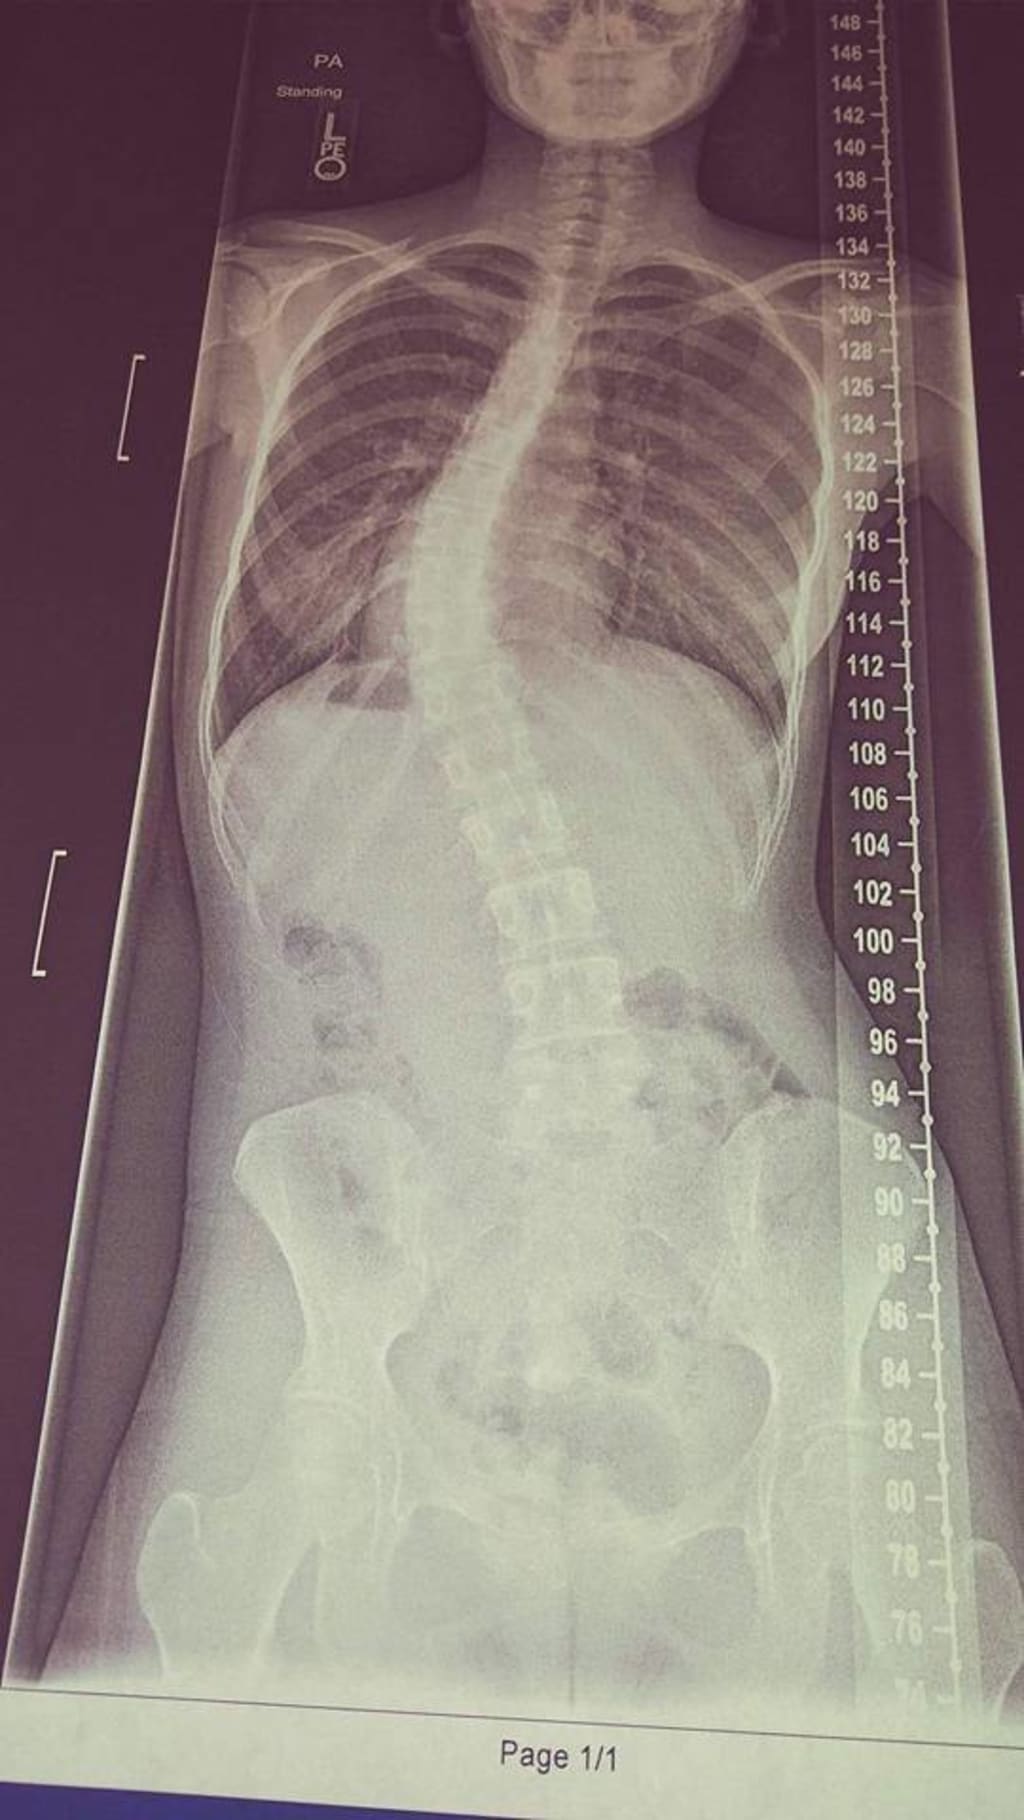

Doctors never really see what you do all day, which makes it easier for me. They don't have to tell me to sit up straight, not slouch because it will mess up my back. They don't have to tell me that I can't stay up all night because it will affect my eyes. Nothing can stop me, that's what I thought till I was in middle school and I found out that I had scoliosis. At first, I didn't care I just thought that it was gonna be fine my spine was different. Till the older I got it got worse and I just felt depressed, I felt like this is bad but I ignored it and thought that the more I ignore it and the more I stand straight it will be better. It didn't, it got worse no matter what.

The worst bullying that I've gotten was when they bullied me for my scoliosis. I can't help something like that. How they found out because I thought to brag about having a bad back would make people pity me and be nice to me, no it didn't. It made them feel like when they look at me they don't look at me like I'm a normal human. No one is normal though unless you're Barbie and have millions of money and sisters and no brothers and get whatever you want.

After my scoliosis though I didn't get bullied anymore. I mean in real life I didn't, online I still did but I know what a block button is. I wish we had really block buttons though, that would make life so much easier. Life isn't easier with extreme scoliosis surgery, you can't do what you want to do anymore, but I still have one thing that the surgery didn't take away from me, which was my life and my personality.